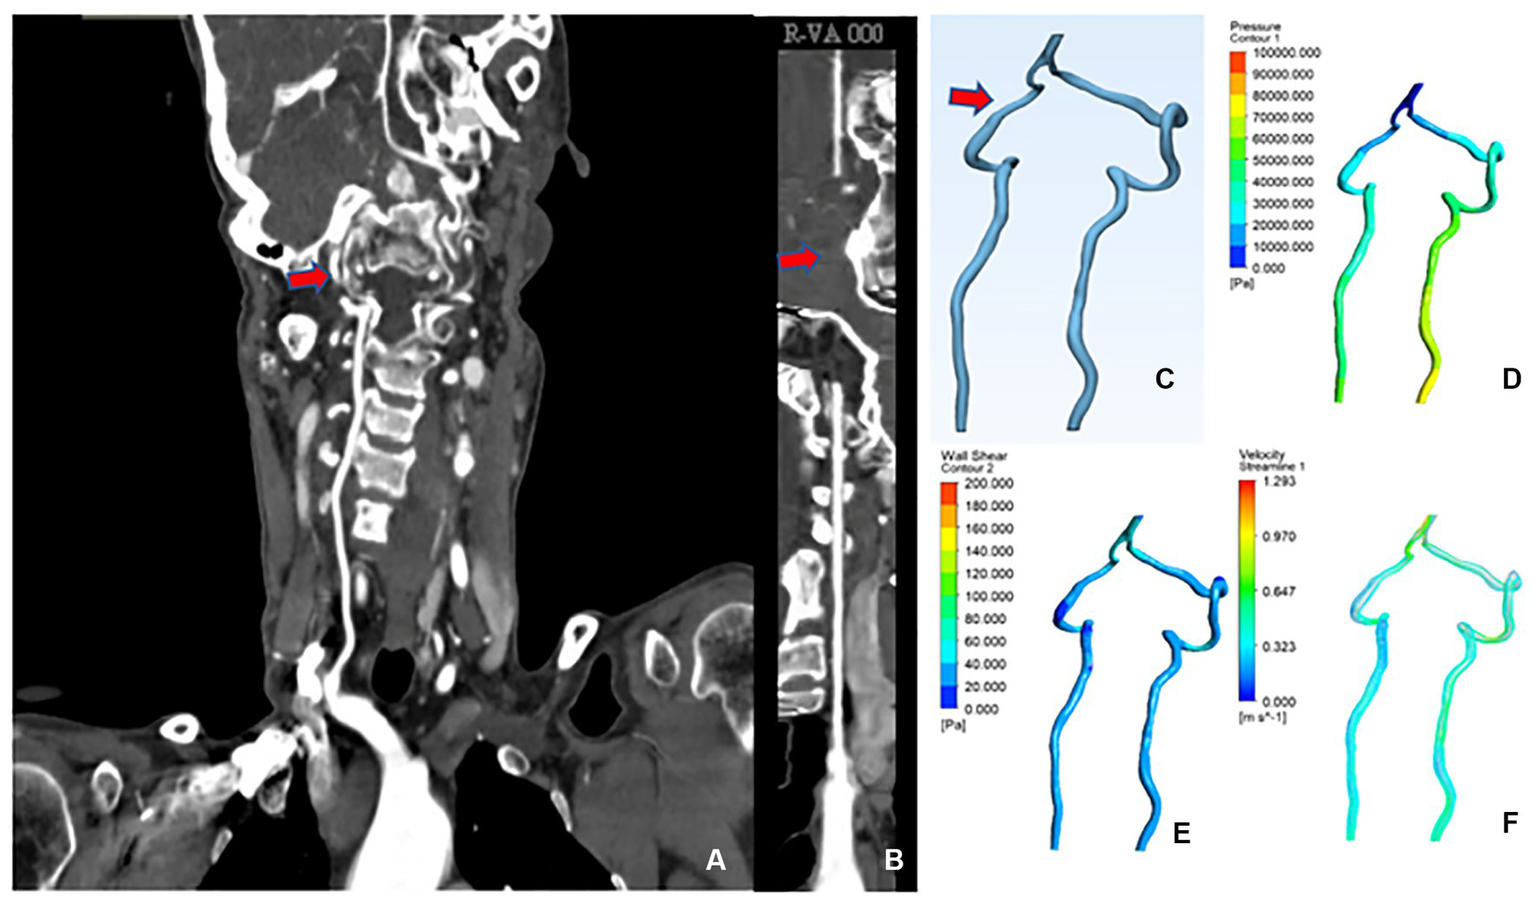

A 60-year-old female was admitted with the chief complaint of “intermittent dizziness with numbness of extremities over 20 years.” A combined head and neck CTA showed: “1. Calcium spots in the wall of the V3 and V4 segments of the right vertebral artery with mild luminal stenosis; 2. Basilar invagination (compression of the right vertebral artery considered).” The patient was diagnosed with “BI,” CFD results showed that the mean lumen diameter of the V3-V4 segment of the VA was lower on the right (2.33 mm) than on the left (3.85 mm); the mean wall pressure was higher on the right (31.20 kPa) than on the left (21.54 kPa); the mean WSS was higher on the right (36.73 Pa) than on the left (41.06 Pa); the mean flow velocity was higher on the right (1.02 m/s) than on the left (0.54 m/s) (Figure 4).

Figure 4

CTA and CFD images of vertebral artery in case 1. (A) Vertebral artery CTA coronal position. (B) Straightened right vertebral artery. (C) CAD model of vertebral artery after smoothing process. (D) Changes in wall pressure gradient at the vertebral artery. (E) Changes in wall shear gradient at the vertebral artery. (F) Vertebral artery flow velocity streamline.